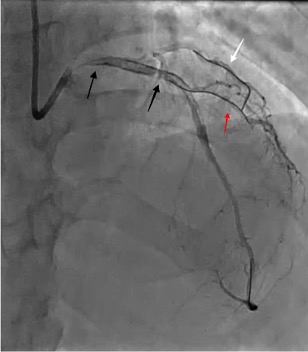

A wire was placed in the diagonal branch prophylactically to preserve side branch patency during main vessel stenting. After successful deployment of a drug-eluting stent (DES) in the LAD, the side branch wire was withdrawn. However, a radiopaque segment remained within the side branch, while the remaining wire fractured and became entrapped behind the stent struts (Figure 2 [black arrows], Video 2).

A coronary snare was used to retrieve the proximal segment of the retained wire. Partial extraction was achieved, but tangled wire fragments remained lodged in the proximal LAD. To stabilize these remnants, an additional DES was deployed to pin the wire against the vessel wall. Although angiography initially appeared satisfactory, intravascular ultrasound (OptiCross, Boston Scientific) proved pivotal by revealing that the wire loops had coiled within the stent, extended retrogradely into the proximal LAD, and reentered the stented segment near the left main stem (LMS) (Figures 2 [red arrow], 3A-C, Video 3).

Final angiography confirmed TIMI-3 flow with no dissection, perforation, or distal embolization; the wire in the side branch remained in place at the end of the procedure (Figures 2 [white arrow], 4A-C, 5, Video 6).